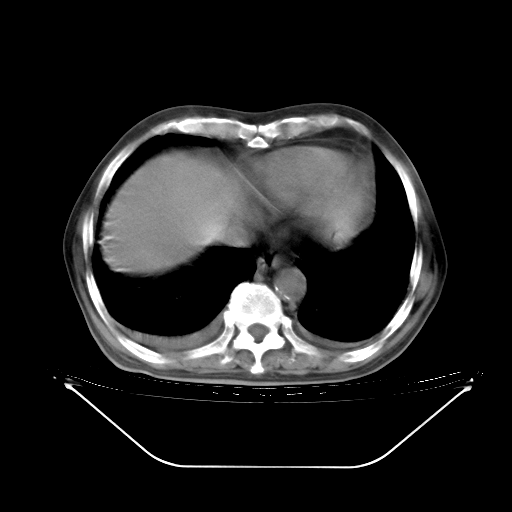

胸腹部CT,诊断意见:左上肺叶钙化灶、左侧胸膜局限性增厚并钙化、胆囊炎。描述部分肺组织呈磨玻璃样改变。